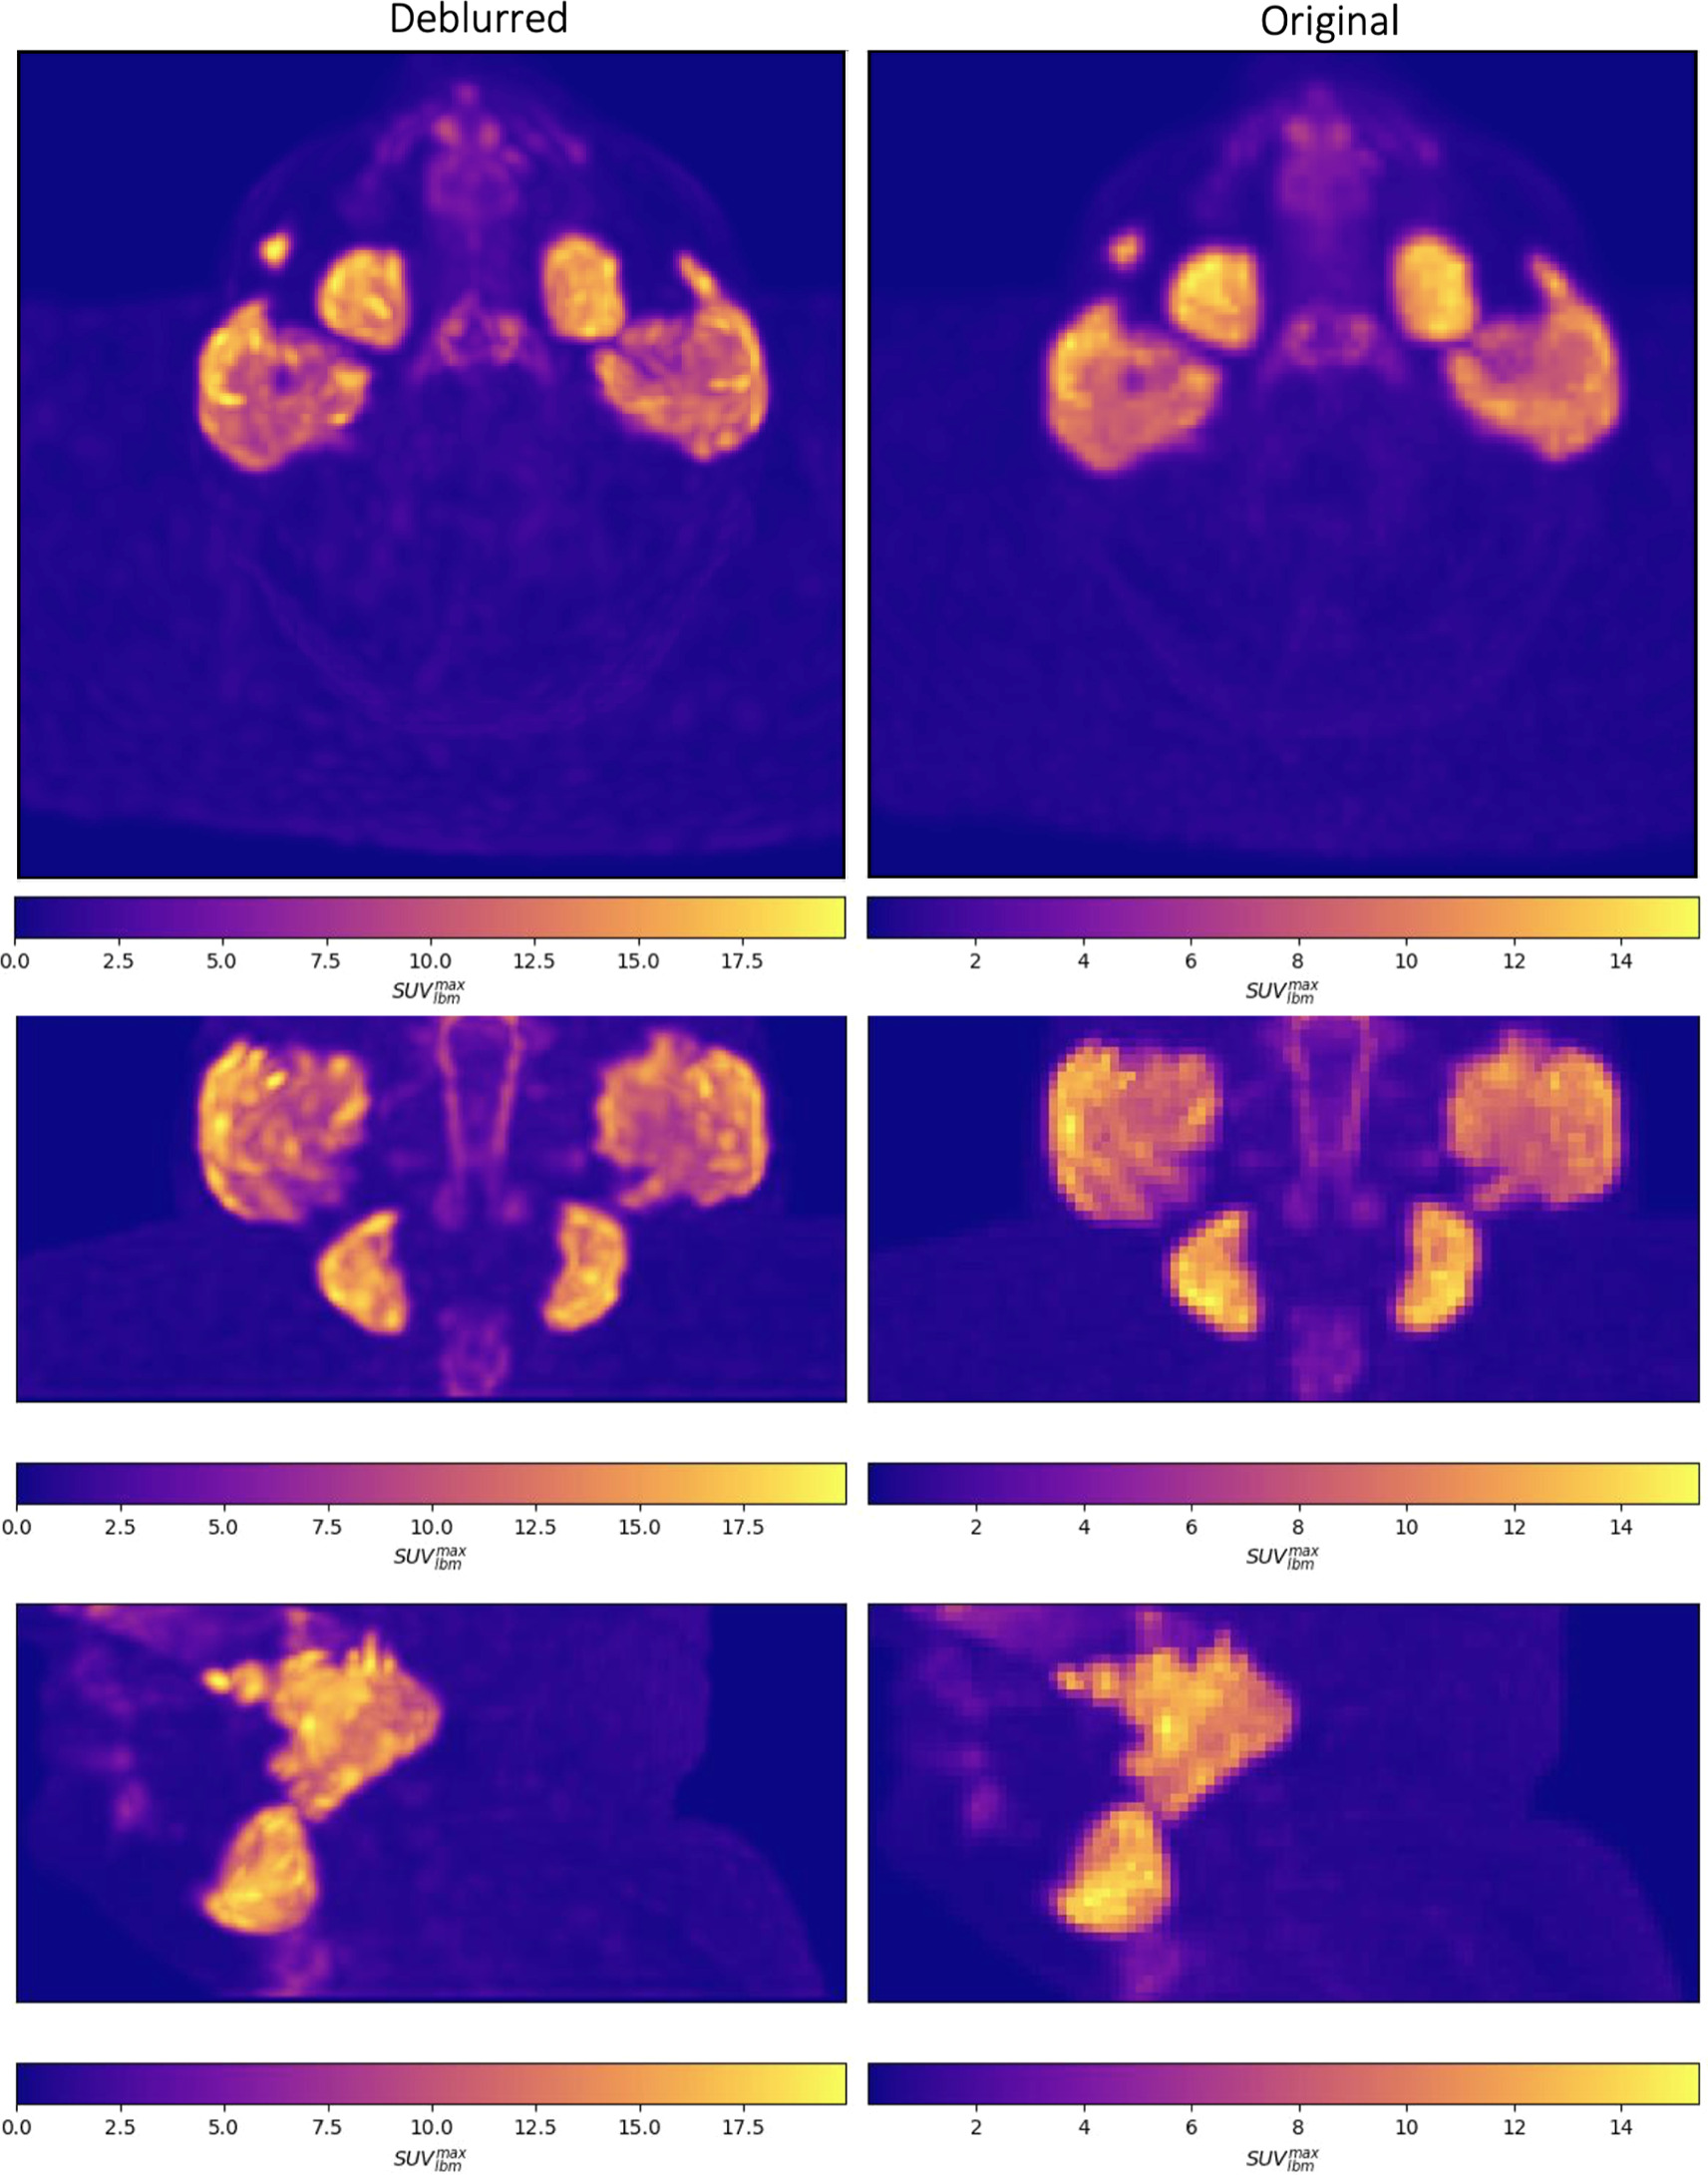

Maximum intensity projection images are shown through the head and neck in figure below.

Maximum intensity projections of deblurred (left) and original (right) PSMA PET images are shown through the head and neck in the axial (top), coronal (middle) and sagittal (bottom) planes